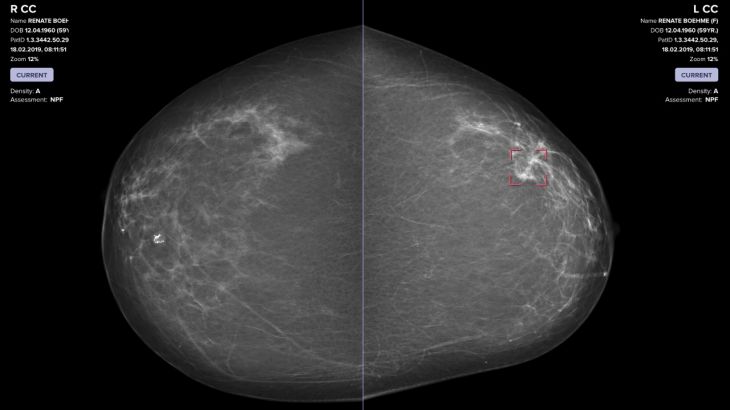

Foto: VARA

Esta inteligencia artificial funciona de dos formas: puede trabajar sola para analizar mamografías o distingue entre los escaneos que parecen normales y los que plantean una preocupación para después remitirlos a un radiólogo.

Esta inteligencia artificial se alimenta de más de 367 mil mamogramas, así como de notas de los radiólogos y de información sobre pacientes con cáncer. Así, la tecnología puede clasificar entre “seguro normal”, “sin confianza” y “cáncer seguro” las mamografías que analiza.